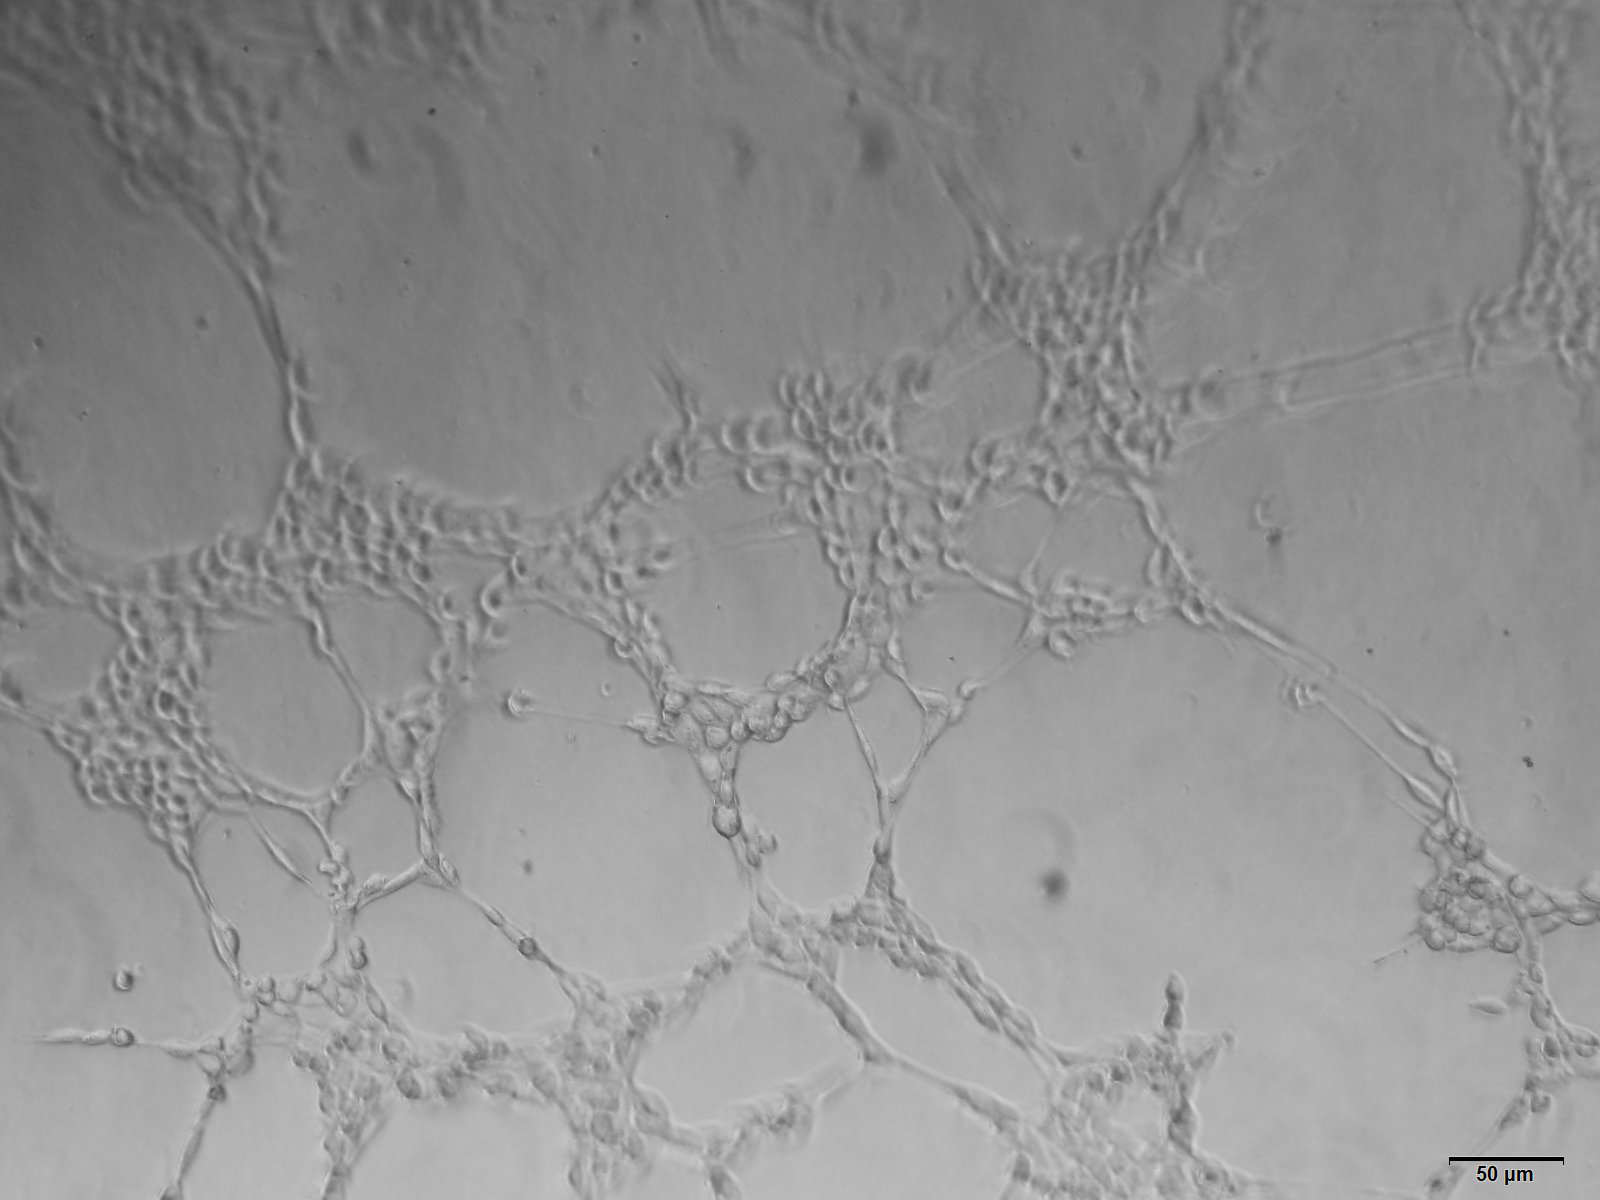

1. 体外实验:Matrigel小管形成实验,将HUEVC细胞接种于均匀铺好matrigel的培养皿中,将含有待测物的培养基或待测细胞上清加入,根据细胞的生长速度实时观察HUEVC细胞是否成管,并对其成管长度、成环数目、结点数目及覆盖面积等进行测量,并通过软件进行统计学分析,也可以根据需要,选择进行免疫荧光染色。

体外实验结果展示